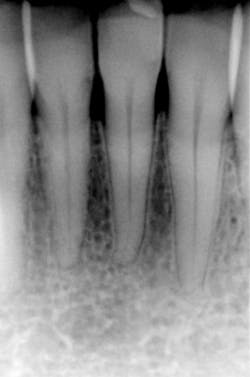

When scatter radiation is decreased by using a rectangular collimator instead of a round collimator, film "fog" is decreased and image quality is increased. Also, the reduction in beam size improves the image definition – its sharpness or resolution. The images at the top of the next page depict the improvement.